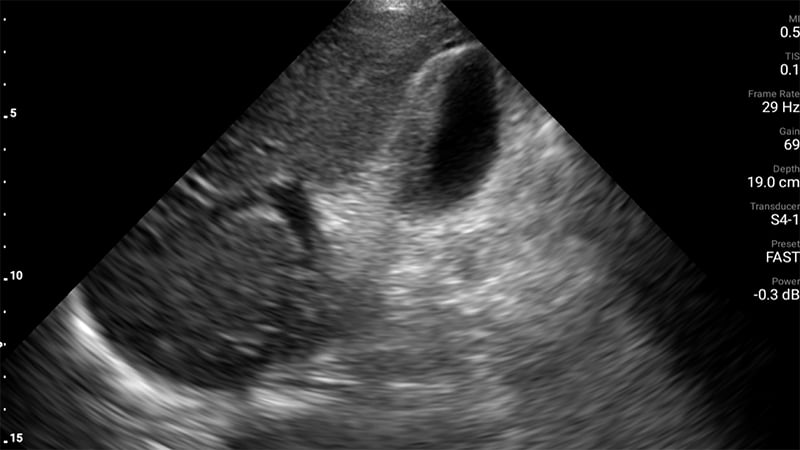

Figures 58A & B. Fluid third-spacing in severe dengue demonstrated via views of free fluid (arrow) in Morrison’s pouch (A), the pleural space (arrow) (B). (Courtesy of Dr. Elijah Katz, Medicines Sans Frontieres)

Figure 58C. Fluid third-spacing in severe dengue demonstrated via view of free fluid (arrow) in the pericardium.